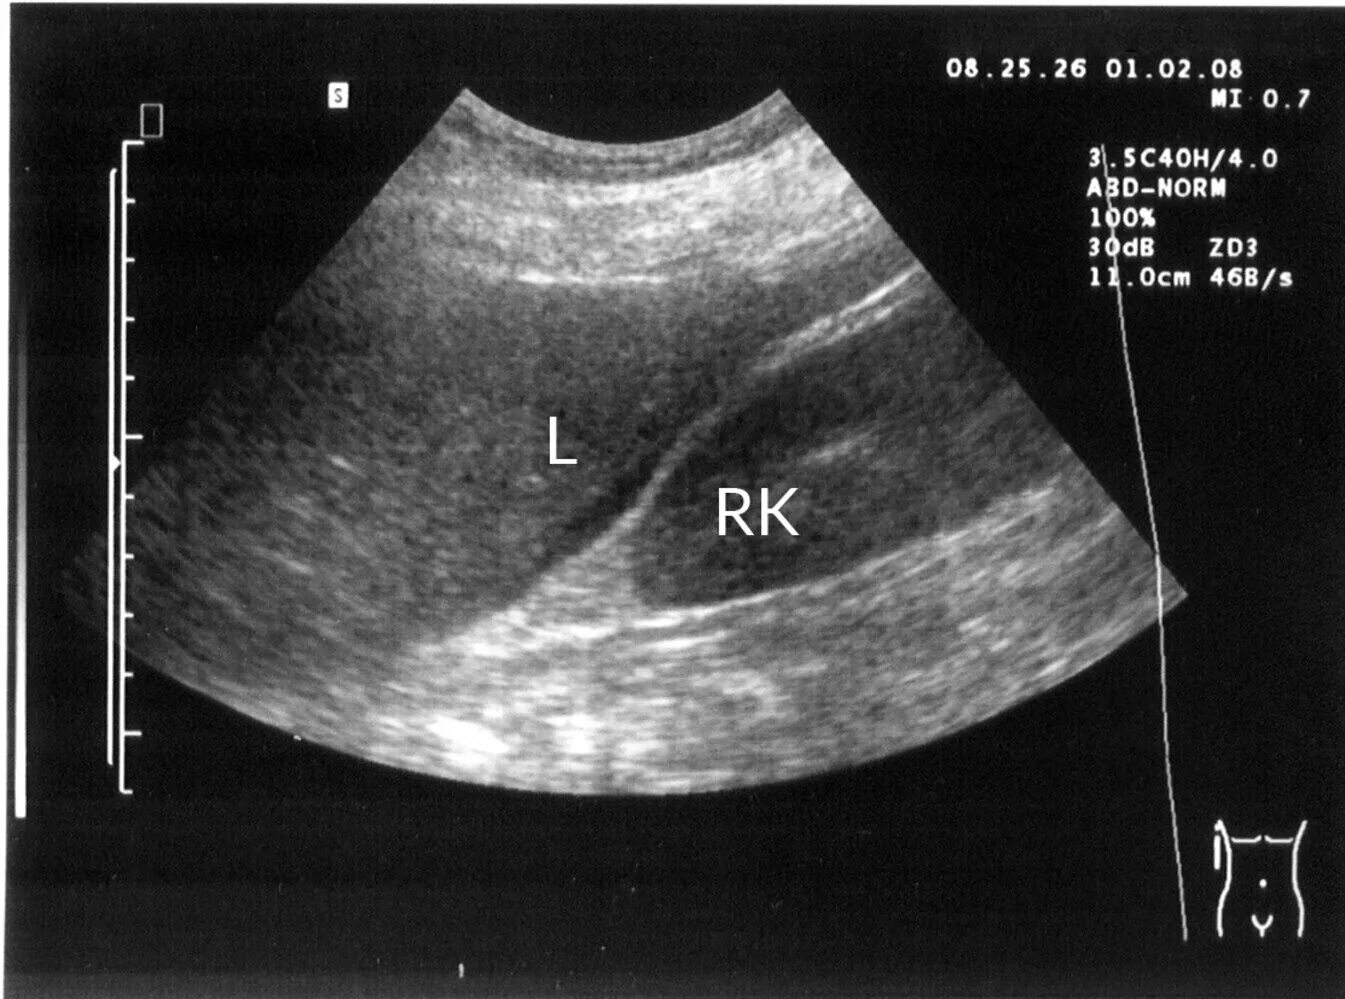

Асцит в малом тазу